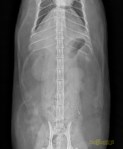

Latérale